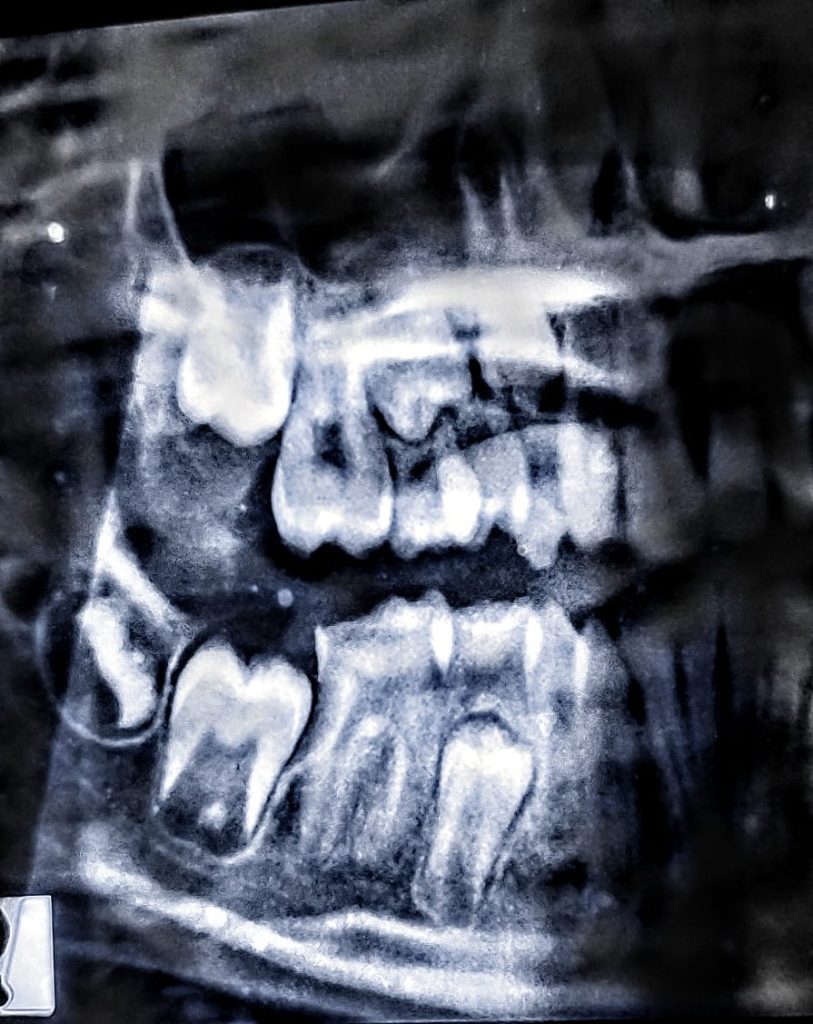

after 6 months, the tooth shows visible apical constrictions and patient had no pain. redone the temporary restoration and again put patient on 6 months follow up for complete apex formation.

after another 6 months the tooth show complete apex formation and patient had no pain, did the root canal treatment, and packed with composite.